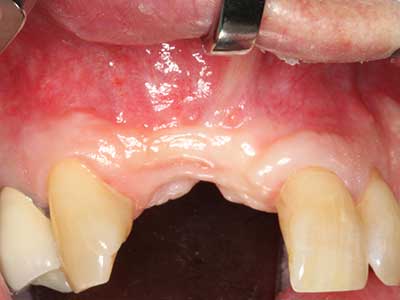

Indication: Bone splitting

Bone tissue is not simply a mineral structure but also contains a substantial proportion of collagen fibres. This means it not only has good compressive strength but also a degree of flexibility, which can be taken advantage of when performing bone augmentations. In the classical expansion procedure using bone splitting, the atrophied alveolar ridge is split longitudinally and carefully expanded after reaching an adequate osteotomy depth (Fig. 13-16), ideally without substantial removal of the periosteum (Brugnami, Caiazzo et al. 2014, Stricker, Fleiner et al. 2014). Screw and plate systems with increasing expansion distance have proven effective in separating the two bone lamellae while remaining below the fracture threshold. In general, residual bone widths of at least 3–4 mm are required (Chiapasco, Zaniboni et al. 2006) to guarantee adequate flexibility and sufficient bone coverage of the future implants. If necessary, a vertical relief osteotomy on one or both sides can improve flexibility. A combination with additional augmentation techniques, particularly on the buccal side, has been described as an alternative to the classical technique.

The splitting procedure is particularly atraumatic and there is no significant loss of dimension when using piezosaws, and there are no significant differences between implants in split jaws and implants in an alveolar ridge without a bone deficit (Chiapasco, Zaniboni et al. 2006, Danza, Guidi et al. 2009). However, sufficient continuous irrigation is essential, particularly with locally restricted and deep splitting to prevent thermal stress in the apical osteotomy regions.